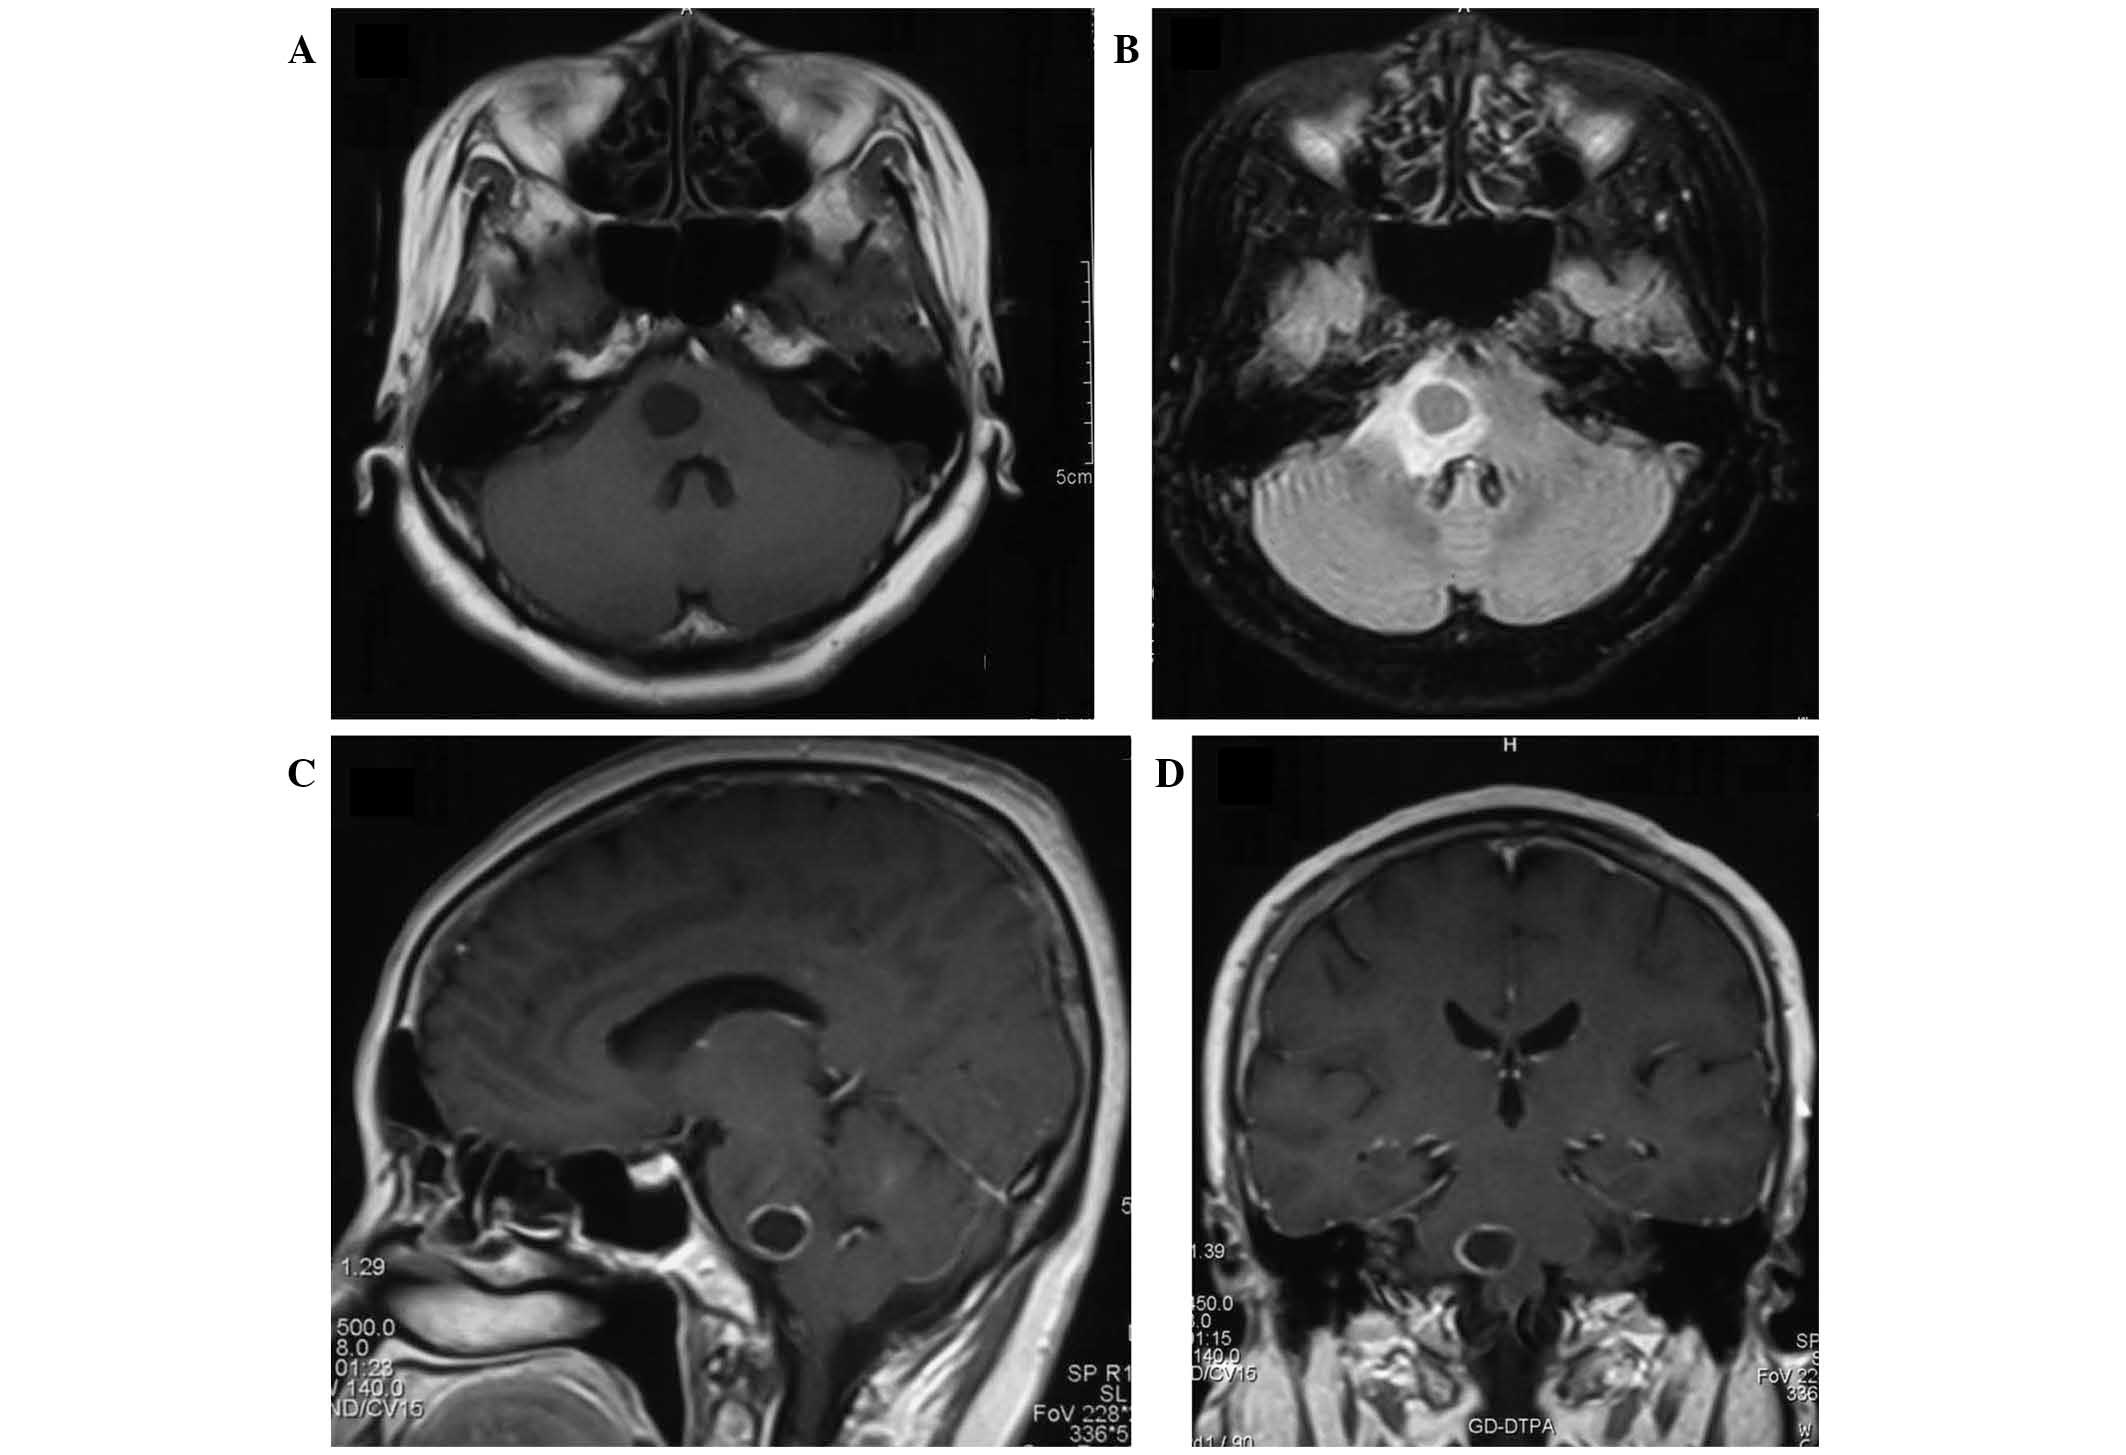

Brainstem metastases have a poor prognosis and are difficult to manage. The present study describes the first case of histopathologically‑confirmed brainstem metastasis originating from lung adenosquamous carcinoma, and discusses the outcomes of treatment by stereotactic aspiration combined with gamma knife radiosurgery (GKRS). A 59‑year‑old female presented with a cystic mass (15x12x13 mm; volume, 1.3 cm3) located in the pons, two years following surgical treatment for adenosquamous carcinoma of the lung. The patient received initial GKRS for the lesion in the pons with a total dose of 54.0 Gy, however, the volume of the mass subsequently increased to 3.9 cm3 over a period of three months. Computed tomography‑guided stereotactic biopsy and aspiration of the intratumoral cyst were performed, yielding 2.0 cm3 of yellow‑white fluid. Histology confirmed the diagnosis of adenosquamous carcinoma. Aspiration provided immediate symptomatic relief, and was followed one week later by repeat GKRS with a dose of 12.0 Gy. The patient survived for 12 months following the repeat GKRS; however, later succumbed to the disease after lapsing into a two‑week coma. The findings of this case suggest that stereotactic aspiration of cysts may improve the effects of GKRS for the treatment of cystic brainstem metastasis; the decrease in tumor volume allowed a higher radiation dose to be administered with a lower risk of radiation‑induced side effects. Therefore, stereotactic aspiration combined with GKRS may be an effective treatment for brainstem metastasis originating from adenosquamous carcinoma.

Figure 2